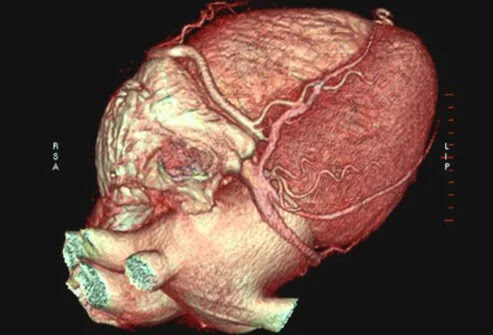

Έλεγχος καρδιακών παθήσεων: Καρδιακή τομογραφία

Μια αξονική τομογραφία καρδιάς δείχνει συσσώρευση ασβεστίου στις στεφανιαίες αρτηρίες για εκείνους που διατρέχουν αυξημένο κίνδυνο καρδιακών παθήσεων και καρδιακής προσβολής.

Η εξειδικευμένη καρδιογραφική τομογραφία (CT) ή «καρδιακή αξονική τομογραφία» μπορεί να παρέχει λεπτομερείς τρισδιάστατες εικόνες της καρδιάς. Οι εικόνες μπορούν να χειριστούν για να αναζητήσουν συσσώρευση ασβεστίου (πλάκα) στις στεφανιαίες αρτηρίες ή να παρέχουν εικόνες τέτοιων εσωτερικών δομών της καρδιάς όπως βαλβίδες ή πάχος τοιχώματος.

Οι αξονικές τομογραφίες μπορούν επίσης να χρησιμοποιηθούν για την εξέταση φυσιολογικής ανατομίας της καρδιάς ή συγγενών ελαττωμάτων. Οι πληροφορίες από έναν αξονικό τομογράφο μπορούν να δώσουν εικόνα για διάφορα προβλήματα καρδιακών παθήσεων.